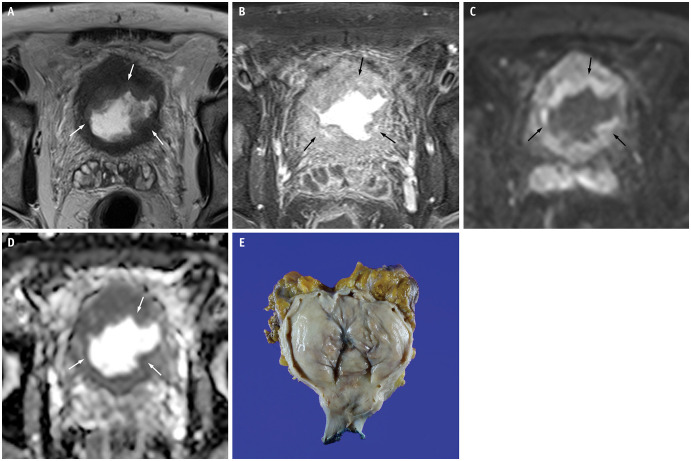

Results: PUC predominantly exhibited diffuse (6/13, 46.2%) or localized (5/13, 38.5%) bladder wall thickening. Diffuse thickening was often associated with a linitis plastica-like appearance. On high b-value diffusion-weighted imaging (DWI), eight and seven cases depending on readers (61.5% and 53.8%, respectively) showed mild hyperintensity or isointensity, with a mean ADC value of 1.1 × 10⁻³ mm²/s. Dynamic contrast-enhanced MRI revealed progressive and prolonged enhancement in 10 cases (76.9%). VI-RADS scores ≥ 4 were observed in 11 cases (84.6%). Histopathological analysis showed that tumors with progressive and prolonged enhancement contained myxoid stroma and some fibrous tissue. Interobserver agreement was excellent for most imaging features, except for good agreement on DWI signal intensity.

Conclusion: PUC demonstrates notable mpMRI features, including localized or diffuse wall thickening (often with a linitis plastica-like appearance), muscle-invasive and advanced disease, progressive and prolonged enhancement patterns, and mild hyperintensity or isointensity on high b-value DWI. These features, which are potentially linked to the myxoid stromal composition of the tumor, suggest that mpMRI may serve as a noninvasive diagnostic tool for this aggressive malignancy. However, further studies with larger cohorts are required to confirm these findings.